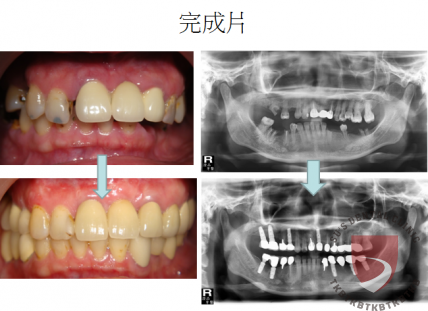

高蛀牙率合併牙周病 牙齒移位

牙周病造成多處缺牙